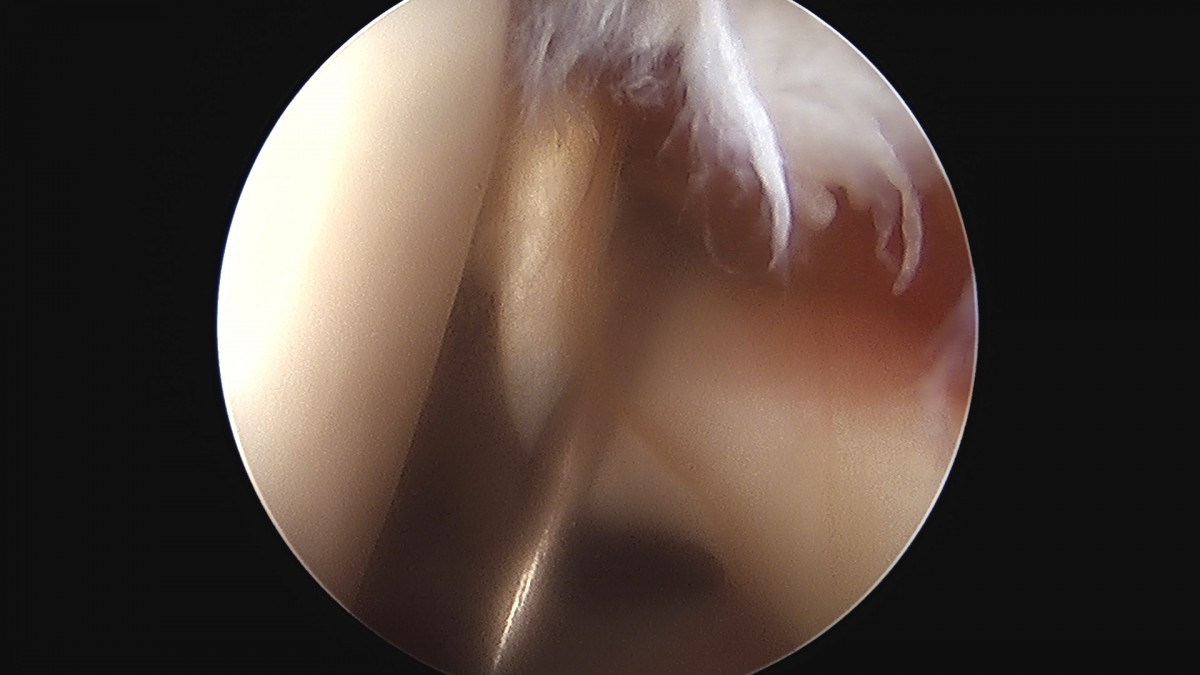

이재상원장님 어깨 견봉하 감압술 김봉O 환자

dae765e4d9ac96aee867c9d6292d8784_1758004120_561.jpg